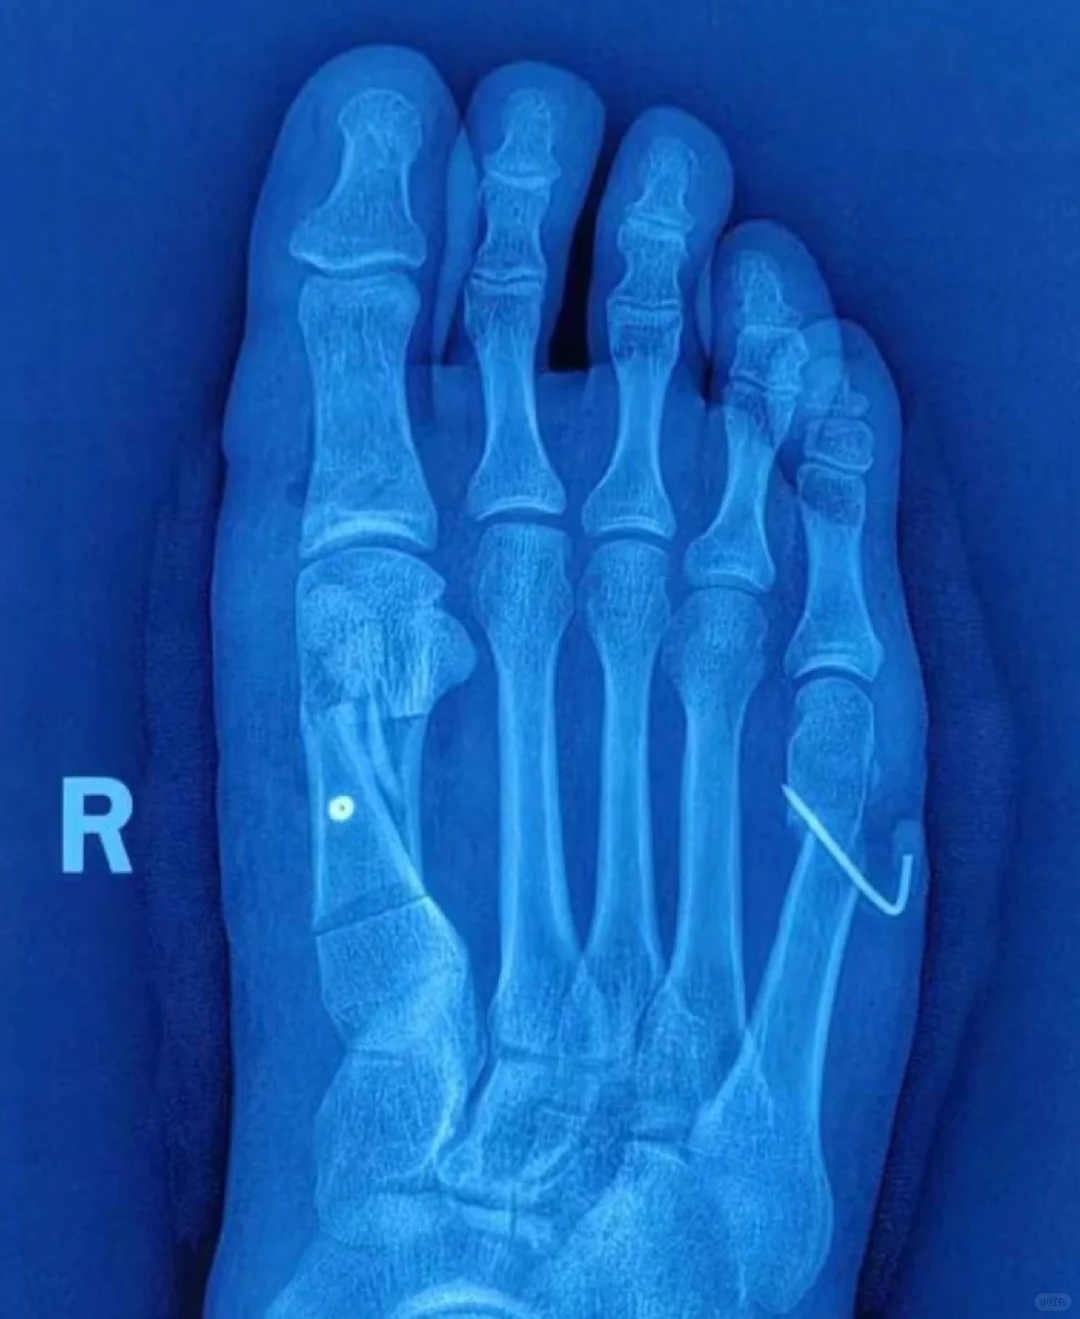

微创术后II型畸形翻修……获得研究突破